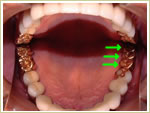

38歳 女性 インプラント埋入数:6本 画像拡大

治療前   治療前

治療後 治療後 治療後